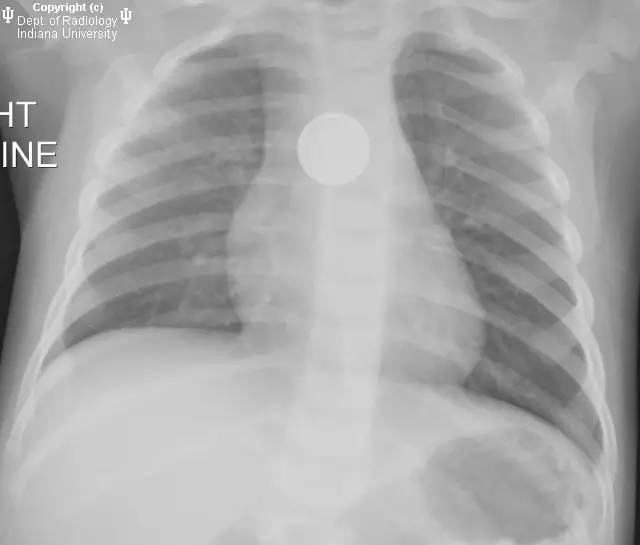

食道异物导致气管食管瘘1例

【病史】婴儿,吞入地板上发现的物品。

【答案】1.E 2.D 医学百科网 | YxBaike.Com

X线片示斜行的圆形不透良应,与食管中段重叠,符合纽扣电池。几天后CT发现较大气管食管瘘,与右主支气管沟通。

【诊断】钮扣电池腐蚀导致气管食管瘘。 医学百科网 | YxBaike.Com